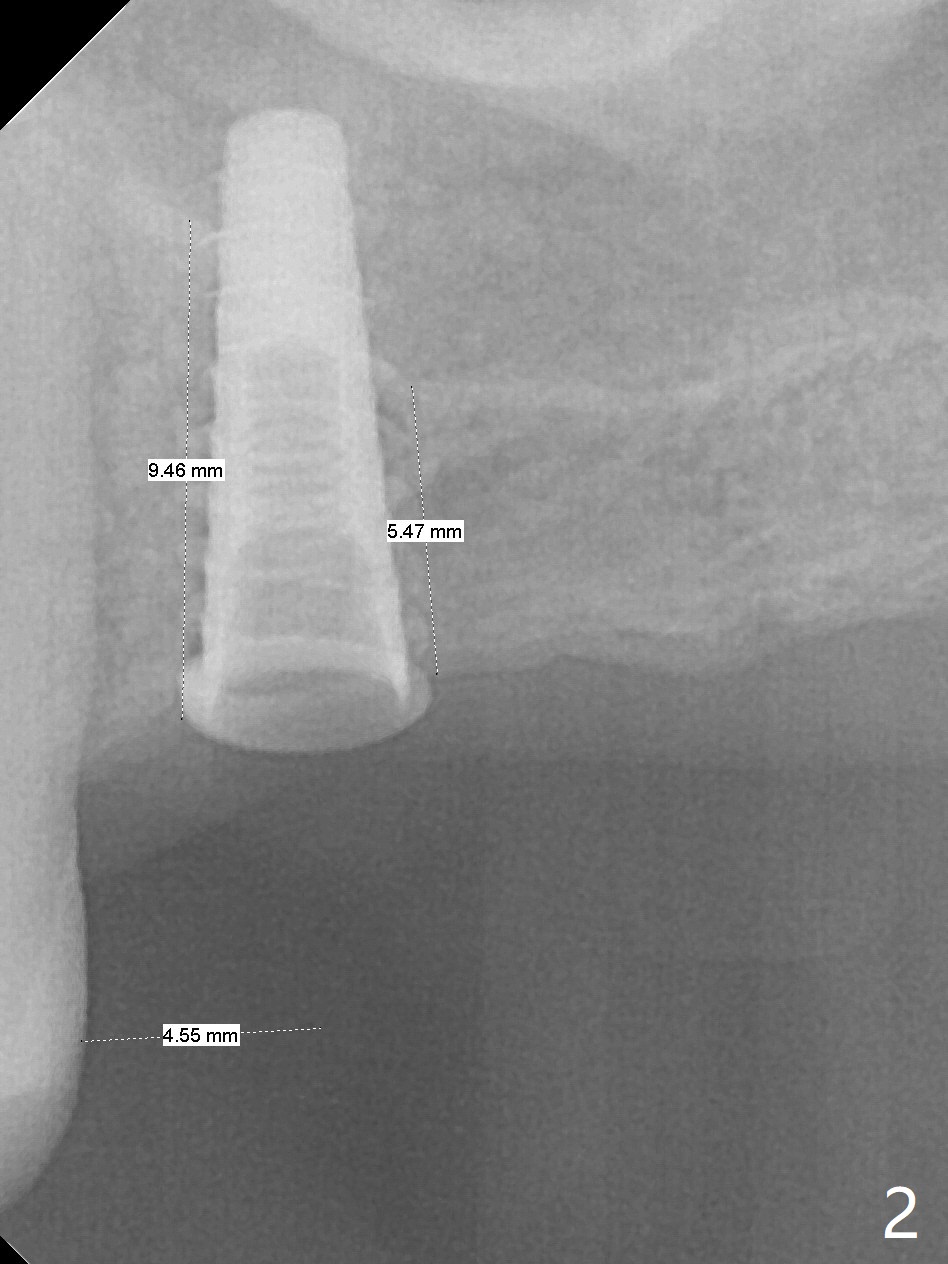

The long 4.8 mm Magic Drill (MD) is used as a tissue punch at the site of #14. After use of a curette to remove the tissue, the MD is used for osteotomy. In fact the osteotomy is mesial with an increase in the osteotomy depth. Magic Lifter, Magic Expander (3 mm) and Magic Drill (3.8 mm) are used to finish sinus lift. Following placement of PRF and Vanilla Graft, a 4.5x11 mm dummy implant is placed (Fig.1,2). The osteotomy seems to be mesial. After use of Lindamann bur distally and 2nd round of PRF membrane and Graft, a 5x9 mm implant is placed > 50 Ncm (Fig.3,4). The final implant appears to remain mesially radiographically. Retrospectively, 1.6 mm pilot drill should have been used with insertion of guide pin after tissue punch. Change in osteotomy position would have been much easier at the early stage. The patient returns for impression 3 months postop; There appears to be space mesial to the implant (Fig.5). The permanent crown will be cemented 2-3 months later. No screw loosens probably related to mesial placement of the implant.